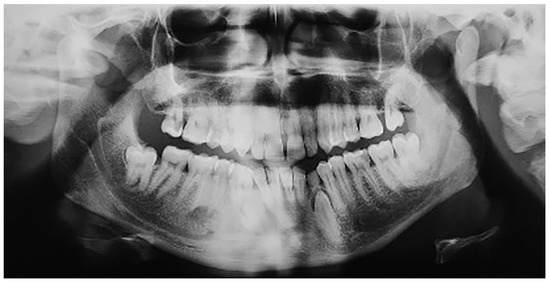

In group B, a total of 13 patients were found to have mandibular canine impaction. Impaction of the canines was bilateral in 1 patient and unilateral in 12 patients, for a total of 14 impacted permanent mandibular canine teeth. Four patients still had retained deciduous canines at the time of diagnosis (Figure 4). In two cases, the impacted canines were transposed in the region of the lateral incisors. Besides these 13 patients with impacted mandibular canines, one (female) of the 640 participants was found to have mandibular canine transmigration. The transmigration was unilateral. In this patient, the primary canine was retained. None of the patients had traumatic episodes, and none of them had systemic disorders. All the patients were asymptomatic.

Figure 4.

Patient with impaction of mandibular canines and retained deciduous canines.